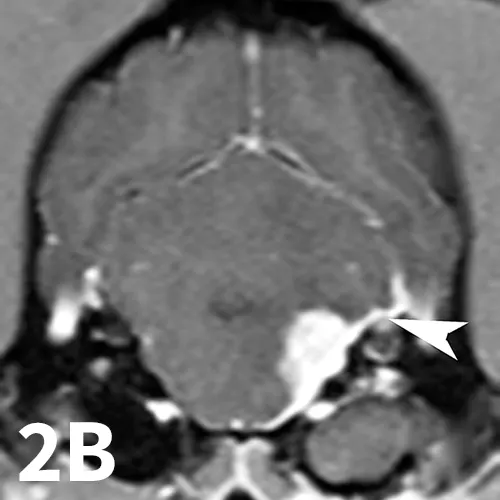

Animals may have erythema and pruritus affecting the external ear or pinna, odor or discharge from the ear, and pain in addition to signs of peripheral vestibular disease. Although diagnosis can be suggested by otoscopy, advanced imaging is superior, as it permits visualization of the osseous bulla and inner ear. The author typically prefers MRI to image dogs suspected of otitis interna because it is superior to computed tomography (CT) for detecting intracranial extension of lesions and detecting other causes masquerading as otitis interna. On MRI, bullae may appear thickened and are usually filled with T2-hyperintense/T1–iso-hypointense (dark) material; abnormal tissue within the bulla usually contrast-enhances T1WI (Figure 2). On T2WI, there may be a loss of signal within the inner ear. Myringotomy and deep ear flush are recommended to identify the underlying infectious agent and assist in removing debris or pus that will prohibit clearance of infection. Antimicrobial therapy is typically continued for 6 to 8 weeks, as bone infection is likely.

Transverse T2WI (A) and T1WI (B) from a 6-year-old cocker spaniel with a 6-month history of left peripheral vestibular disease that acutely worsened, with signs consistent with central localization. The left middle ear cavity is filled with T2-hyperintense material (arrowhead). The left inner ear is hypointense (arrow) compared with the right side. In addition, the left medulla and cerebellum contains patchy T2-hyperintense lesions. T1 postcontrast images show enhancement of the meninges (arrowhead) and a mass-like, enhancing lesion adjacent to the internal acoustic meatus. These findings are consistent with chronic otitis interna and media with secondary extension into the meninges and central nervous system.